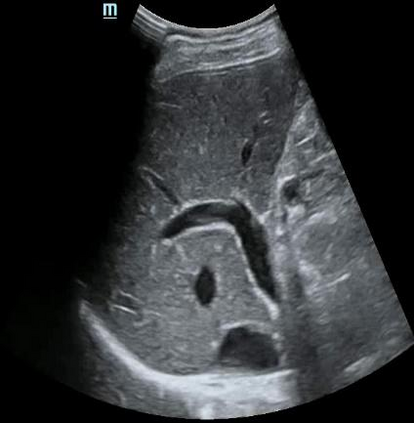

Most deep neural networks (DNNs) based ultrasound (US) medical image analysis models use pretrained backbones (e.g., ImageNet) for better model generalization. However, the domain gap between natural and medical images causes an inevitable performance bottleneck. To alleviate this problem, an US dataset named US-4 is constructed for direct pretraining on the same domain. It contains over 23,000 images from four US video sub-datasets. To learn robust features from US-4, we propose an US semi-supervised contrastive learning method, named USCL, for pretraining. In order to avoid high similarities between negative pairs as well as mine abundant visual features from limited US videos, USCL adopts a sample pair generation method to enrich the feature involved in a single step of contrastive optimization. Extensive experiments on several downstream tasks show the superiority of USCL pretraining against ImageNet pretraining and other state-of-the-art (SOTA) pretraining approaches. In particular, USCL pretrained backbone achieves fine-tuning accuracy of over 94% on POCUS dataset, which is 10% higher than 84% of the ImageNet pretrained model. The source codes of this work are available at https://github.com/983632847/USCL.